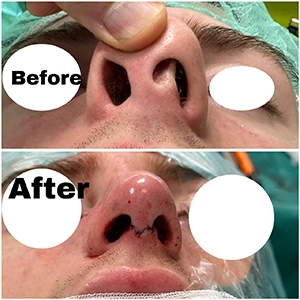

🎯 انتخاب بهترین جراح بینی در تهران

اگر به دنبال بهترین جراح بینی در تهران هستید، تجربه، نمونه کارهای موفق، ارتباط حرفهای با بیمار و آشنایی با تکنیکهای مدرن جراحی، معیارهایی مهم برای انتخاب شما هستند. حتماً عکسهای قبل و بعد عمل بینی بیماران را ببینید و در جلسه مشاوره تمام انتظارات خود را مطرح کنید.